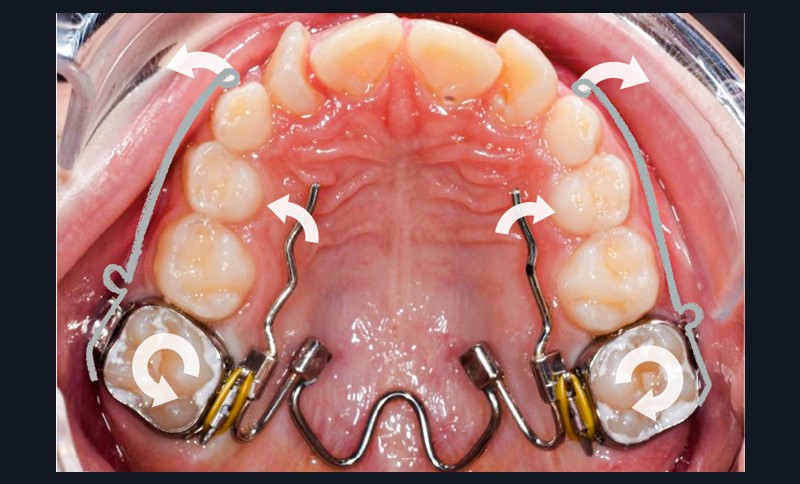

Des bagues molaires sont essayées et adaptées sur 16 et 26 et un arc transpalatin à mémoire de forme (Nitanium Palatal Expander -Ortho Organizers, USA) dont la dimension est sélectionnée à partir de la mesure de la distance inter-molaire mandibulaire est ligaturé à celles-ci hors bouche. L’ensemble est scellé avec un ciment verre-ionomère après refroidissement au spray à -45 °C de la partie en NiTi pour insertion facilitée.

Sept jours après la pose du dispositif, une intervention chirurgicale est réalisée sous anesthésie locale lors de laquelle a lieu le collage de dispositifs de traction sur 13 et 23. Les canines temporaires sont extraites dans le même temps opératoire.

Trois jours plus tard, des bras en TMA .017 x .025 habillés d’une gaine de protection avec omega au contact des tubes des premières molaires et dont l’extrémité mésiale forme une boucle sont ligaturés aux dispositifs collés de traction.

Les maillons de la chaînette du dispositif de traction sont sectionnés progressivement de manière bilatérale à chaque rendez-vous à mesure que les canines sont déplacées en direction vestibulaire et le bras TMA est systématiquement religaturé au premier maillon transmuqueux avec une ligature métallique .010. L’ensemble est sécurisé par une goutte de composite fluide photopolymérisé.

Une fois que la partie en alliage à mémoire de forme de l’arc transpalatin a retrouvé sa forme initiale, l’arc est désinséré. Les U latéraux et les lames d’insertions en acier sont réglés dans les trois sens de l’espace à l’aide d’une pince 139 pour corriger l’inclinaison mésio-distale, le torque et augmenter la dérotation de 16 et 26 pour assurer une traction supplémentaire des canines incluses en direction vestibulaire. Les bras d’expansion des secteurs latéraux de l’arc transpalatin sont également sectionnés. Les bras vestibulaires en TMA sont activés dans le sens vertical pour une traction des canines vers le plan occlusal.